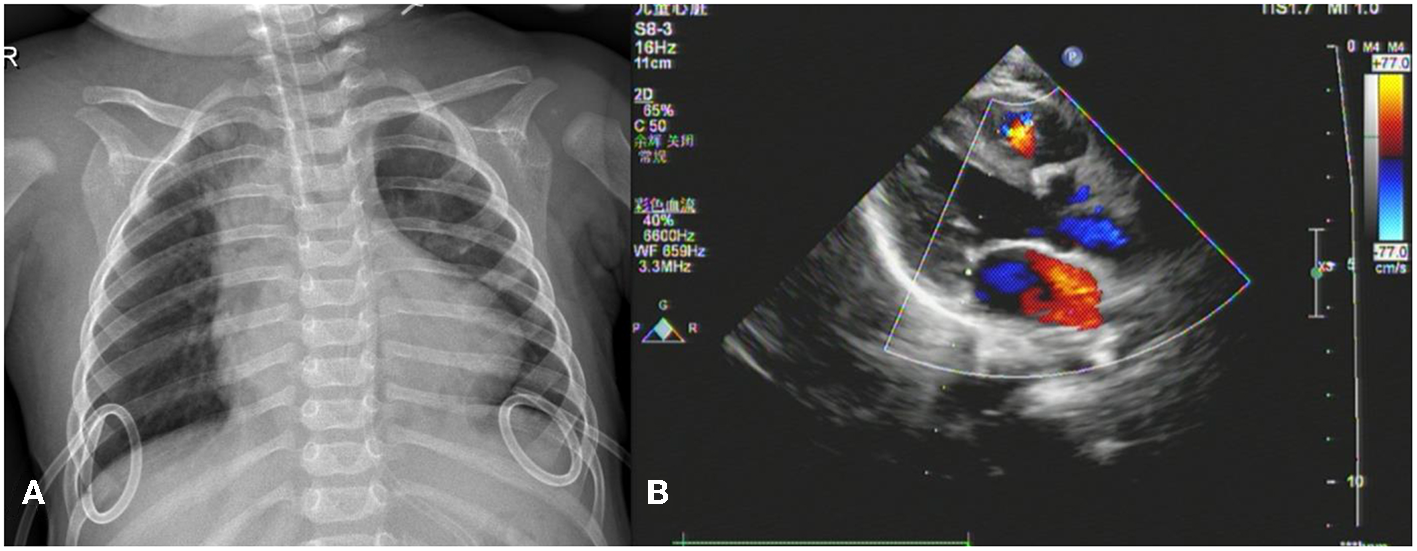

Thereafter, the vital signs were stable. There was no fever and the infection indicators were not high. The infant's circulatory and respiratory conditions were stable, and tracheal intubation was expected to be removed if there was no change in condition. An acute alteration occurred in the patient's condition on postoperative day seven after chest radiography. The patient developed an unstable condition with a reduced heart rate, hypotension, and hypoxemia that progressed rapidly to cardiac arrest. Effective CPR was initiated and the possible causes of cardiac arrest were evaluated. Unplanned extubation was identified as the most probable cause of cardiac arrest. After 10 min uninterrupted resuscitation, spontaneous respiratory and normal circulation returned. However, clinical observation revealed that the pre-existing thoracic drainage tube on the right side continuously drained hemorrhagic fluid, which was complicated by decreasing hemoglobin and blood pressure. The patient presented with progressive anemia and hypovolemic shock. After aggressive fluid resuscitation, hemorrhagic shock persisted. A bedside ultrasound was performed, and pericardial tamponade and effusion were not found. In addition, no significant pleural effusion was observed on repeat chest radiography (Figure 1). Therefore, emergency exploratory thoracotomy was required, given that intercostal vessel injury or intrathoracic injury during the rescue process might be possible reasons for persistent thoracic cavity bleeding. After informed consent was obtained from the immediate family, exploratory surgery was performed. The chest was entered through the original median sternal incision, and a small number of blood clots and fresh bleeding were observed in the mediastinum. After cleaning the accumulated blood, exploration continued to reveal active bleeding in the anterior branch of the right ventricular coronary artery which had a half a millimeter long tear (Figure 2). Because the tear was small, we repaired it directly using a 7-0 Prolene suture. The bleeding stopped immediately, and the patient's condition gradually stabilized. In addition, a 1 cm tear was found in the right pleura that communicated with the anterior mediastinum. Opening of the right pleura and continued exploration of the right thoracic cavity revealed no active bleeding. During 30 min observation, no ST segment changes were observed on electrocardiography. After sternal closure, the patient was returned to the cardiac intensive care unit (CCU). The patient's postoperative ECG showed no significant ST-T changes (Figure 3). The patient subsequently recovered successfully and was extubated on day three after exploratory thoracotomy and coronary repair surgery, transferred out of the CCU on day six, and discharged on day 15. At the follow-up 3 months after discharge, the patient's cardiac function had recovered well and blood indicators were normal.

Figure 1

Imaging findings. (A) Chest X-ray shows bilateral drainage tubes and no obvious signs of pleural effusion. (B) No signs of pericardial tamponade or pericardial effusion on echocardiogram in left ventricular long-axis view.